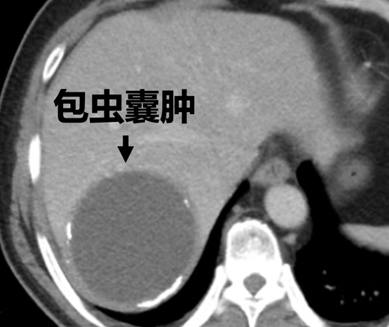

可等来的不是病情好转,而是身体的各种不适。吐尔逊经常疼得直不起腰,再次来到第一师医院检查,包虫的直径已疯涨到9厘米大小(差不多一个小皮球一样),紧紧压迫到周围脏器。

“患者有两次开腹手术史,腹腔内情况可能比预想的更复杂。”接诊后,第一师医院党委副书记、院长马涛立刻带领普外科一病区团队开会讨论。两次开腹手术早已让吐尔逊的腹腔“面目全非”:肠管与腹壁、肝脏紧密粘连,原本清晰的解剖结构变得模糊不清,就像被胶水粘住的毛线团,稍不注意就可能扯破肠管或损伤血管。“传统开腹手术不仅会再次扩大创伤,还可能因粘连导致术中出血、术后肠瘘等风险,对患者身体打击太大。”马涛院长的话,点出了手术的核心难题。“这次我们不仅要把这个顽固的包虫囊肿“一锅端”,还要争取在微创下完成,面对这块“难啃的硬骨头”,更要展示我们一师医院微创外科的硬核实力!”马涛院长术前信心满满。

团队最终决定采用“腹腔镜下肝包虫囊肿切除+肠粘连松解术”的方案,既要在微创条件下解开腹腔里的粘连结,又要完整取出9厘米的包虫囊肿,不能有丝毫破裂(一旦包虫囊液泄漏,可能引发腹腔感染),每一步都要特别谨慎。

手术当天,马涛院长带领普外科一病区副主任李永崇、主治医生刘小龙等医护人员站上手术台。腹腔镜镜头下,粘连的肠管与腹壁及肝脏紧紧贴在一起,医生们手持精细器械,以毫米级的动作一点点分离粘连组织,每分离一处都要反复确认血管和肠管位置,避免误伤。由于包虫囊肿位于肝脏右后叶,且与膈肌粘连紧密,无法采取常规方法游离肝脏,马涛院长术中创新采用了前入路原位切除的方法,经术中B超定位包虫囊肿的边界后,通过牵引悬吊局部肝脏实质,将囊肿从正常肝组织中完整剥出,再小心翼翼地游离囊肿与膈肌的粘连,最终通过腹部小切口将这个9厘米的“麻烦包”完整取出。经过数小时奋战,手术顺利完成。